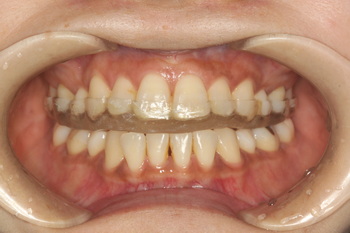

顎関節治療での短期使用(6ヶ月以内)を前提とした熱可塑性樹脂+即時重合レジンスプリント,

保険請求では口腔内装置2

(印象45+装着830+調整220)アクリルスプリントに比べるとかなり点数が低くなります

耐摩耗性が低く着色汚れが生じやすいのが欠点ですが,装着時はほとんど無調整でセットが可能です.

熱可塑性樹脂+即時重合レジン 2年間使用 変色が強く摩耗も大きいのが分かります

顎関節症は装着の容易な2型,長期使用するブラキシズム症例では1型が良いのでは無いでしょうか.